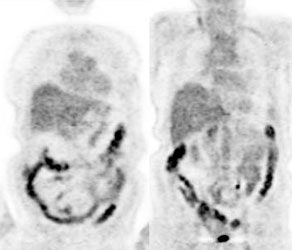

Bladder cancer: Dilute urinary activity in this patient's bladder allowed accurate detection of their bladder cancer (white arrows on CT, black arrows on PET scan). In general, urinary excretion of FDG limits evaluation of urinary tract malignancies, however, hydration and diuresis can improve diagnostic accuracy. |

|

|